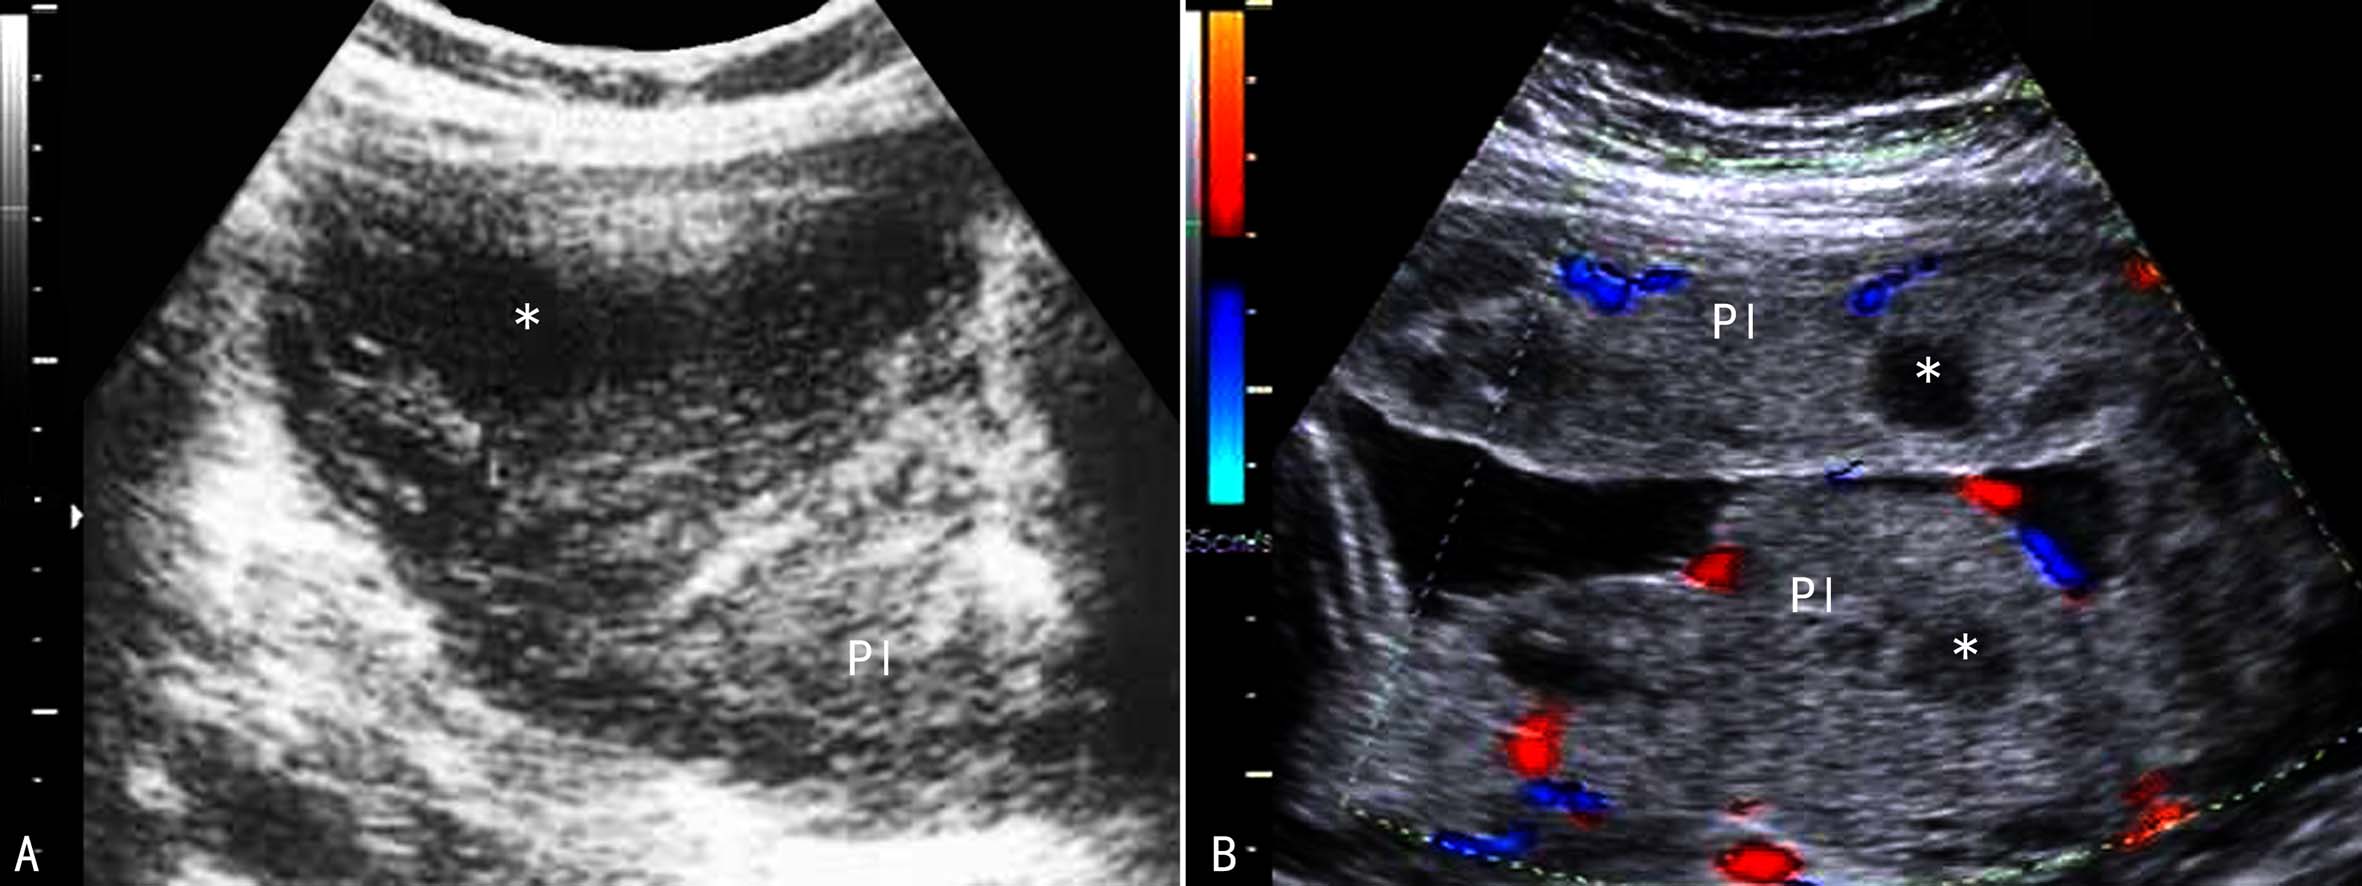

胎盘梗死的发生率比较高,有报道30%~40%的胎盘可以发现大小不等的胎盘梗死,但多数梗死灶较小或发生于胎盘边缘区域而不引起明显的临床表现,以至于胎儿出生后也不被临床医生注意。胎盘梗死可以发生在胎盘的任何部位,但多发生在胎盘母体面实质内,单发或多发,由局部血管梗死、缺血、坏死所致,形成大小、形态不一梗死灶。已经发现,母体患有高血压、肾脏疾病、妊娠高血压综合征、糖尿病等疾病时胎盘梗死的发生率较高。

2D-US胎盘梗死显示为胎盘实质内单发或多灶性低回声或无回声区,多数直径在1~2cm,有一定的形态和明确的范围,边缘不清楚,内部回声分布均匀或不均匀(图3),有时可见少数稍强的点状回声。多数情况下羊水和胎儿发育正常,梗死区较大时可引起胎儿宫内生长迟缓。需要注意的形成胎盘内的多发性低回声的还有绒毛周围纤维蛋白沉积、胎盘转移瘤等;胎盘血池显示为胎盘实质内的无回声,检查过程中有时可显示该无回声在子宫收缩下或位于前壁胎盘内的血池在加压时可见其形态的变化;无回声内有时可显示移动的点状回声,但由于移动的速度很慢、超声多普勒检查多数无法记录其血流信号。

图3胎盘梗死声像图